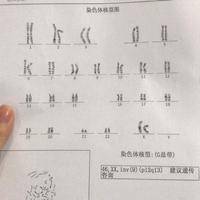

9号染色体壁间倒位必须做试管才能生出正常的孩子吗?

问题描述:上周天的时候和老公去做了备孕前的检查,原本因为我俩应该没什么生育问题,但没想到查出来我老公存在染色体问题。从单子上看显示的是“9号染色体壁间倒位”,我之前听说染色体异常会影响到胎儿健康所以想问问只有做试管才能生育正常的孩子吗?最佳回答:不一定非要做试管。9号染色体的壁间倒位是一种遗传学异常,可能影响生育不过也要看具体异常情况才能决定适合采取哪种生育方式。大多数情况下,壁间倒位可能不会对健...